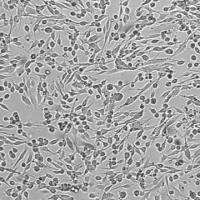

上皮样细胞(Epithelial-like)

贴壁生长(Adherent)

| 细胞形态 | 上皮样细胞(Epithelial-like) |

| 生长特性 | 贴壁生长(Adherent) |